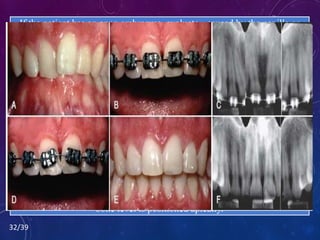

OPEN GINGIVAL EMBRASURES

• The presence of a papilla between the maxillary central incisors

is a key esthetic factor in any individual.

• This open space is usually due to one of three causes:

 Tooth Shape, Root Angulation, Or Periodontal Bone Loss.

• The interproximal contact b/w the maxillary central incisors

consists of 2 parts- tooth contact, the papilla.

• Ratio of papilla to contact is 1:1.

32/39

Another possibility is to erupt adjacent teeth when the interproximal

bone level is positioned apically.

This type of movement may help create a more esthetic papilla between

two teeth despite alveolar bone loss.

By closing open contacts, the interproximal gingiva can be squeezed and

moved incisally.

In some situations, a deficient papilla can be improved with orthodontic

treatment.

Papilla is the problem, the cause is lack of bone support due to an

underlying periodontal problem.

If the patient has an open embrasure, evaluate - caused by the papilla or

the tooth contact.

32/39 Another possibility isto erupt adjacent teeth when the interproximal bone level is positioned apically. This type of movement may help create a more esthetic papilla between two teeth despite alveolar bone loss. By closing open contacts, the interproximal gingiva can be squeezed and moved incisally. In some situations, a deficient papilla can be improved with orthodontic treatment. Papilla is the problem, the cause is lack of bone support due to an underlying periodontal problem. If the patient has an open embrasure, evaluate - caused by the papilla or the tooth contact.

• #32 This patient had a PROTRUSIVE BRUXING HABIT that had caused severe abrasion of the maxillary anterior teeth , resulting in the loss of over half of the crown length of the incisors (A and B). Two possible options existed for gaining crown length to restore the incisors. One possibility was an apically positioned flap with osseous recontouring, which would expose the roots of the teeth. The less destructive option was to intrude the four incisors orthodontically, level the gingival margins (C and D), and allow the dentist to restore the abraded incisal edges (E and F). The orthodontic option was clearly successful and desirable in this patient.

• #34 Figure 51-14 This patient initially had overlapped maxillary central incisors (A), and after initial orthodontic alignment of the teeth, an open gingival embrasure appeared between the centrals (B). Radiograph showed that the open embrasure was caused by divergence of the central incisor roots (C). To correct the problem, the central incisor brackets were repositioned (D), and the roots were moved together. This required restoration of the incisal edges after orthodontic therapy (E) because these teeth had worn unevenly before therapy. As the roots were paralleled (F), the tooth contact moved gingivally and the papilla moved incisally, resulting in the elimination of the open gingival embrasure.